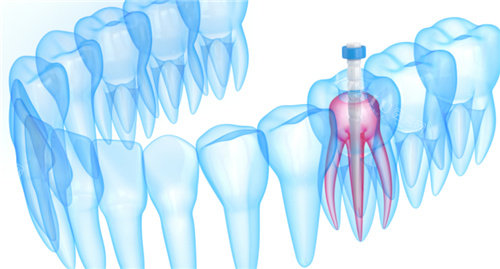

前牙根管治疗:300元起/颗

后牙根管治疗:600元起/颗